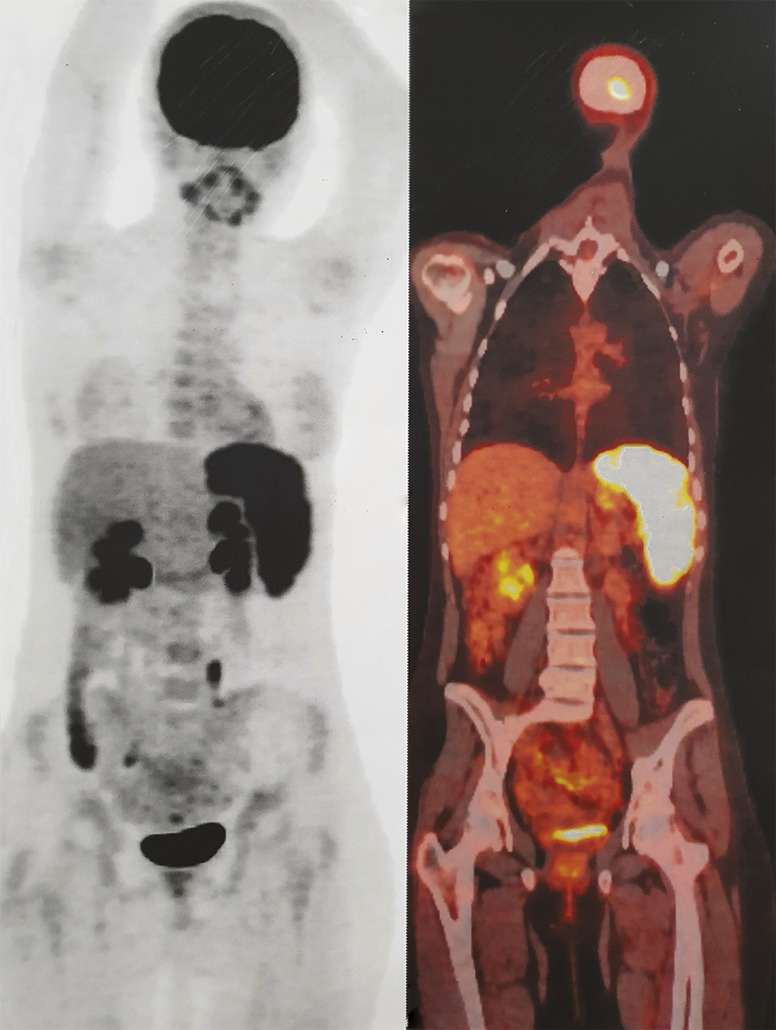

Cette jeune fille de 17 ans, sans antécédents particuliers, décrivait depuis trois mois une fièvre, des sueurs nocturnes, des céphalées, une asthénie, et un amaigrissement de 10 kg en deux mois. À l’examen, on notait une fièvre à 38 °C et une tachycardie à 110 batt/min. La biologie montrait un syndrome inflammatoire, avec une protéine C-réactive à 114 mg/L. Les bilans infectieux et immunologique étaient normaux. Une tomographie par émission de positons (TEP) au 18F-FDG objectivait une splénomégalie intensément hypermétabolique, pathologique, de fixation hétérogène (fig. 1 ). L’étude histologique (fig. 2 ) de la pièce de splénectomie (fig. 3 ) avait posé le diagnostic de tuberculose splénique. Sous traitement antituberculeux, une amélioration clinique et biologique avait été obtenue.